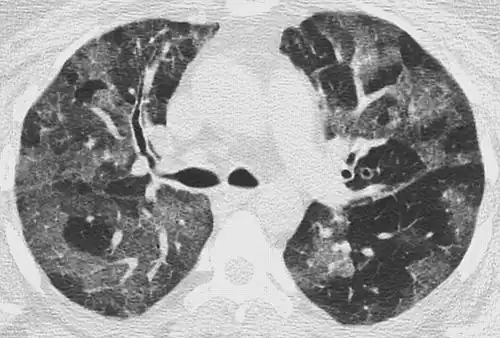

Crazy paving

The crazy paving pattern may occur when there is both interlobular and intralobular widening. This sometimes resembles a road paved with irregular bricks or tiles. It is typically diffuse, involving larger areas of one or multiple lobes. There are a variety of potential causes, including Pneumocystis pneumonia, late-stage adenocarcinoma, pulmonary edema, some types of idiopathic interstitial pneumonias, diffuse alveolar hemorrhage, sarcoidosis, and pulmonary alveolar proteinosis.[6] COVID-19 has also been shown to occasionally cause GGOs with a crazy paving pattern.[11]